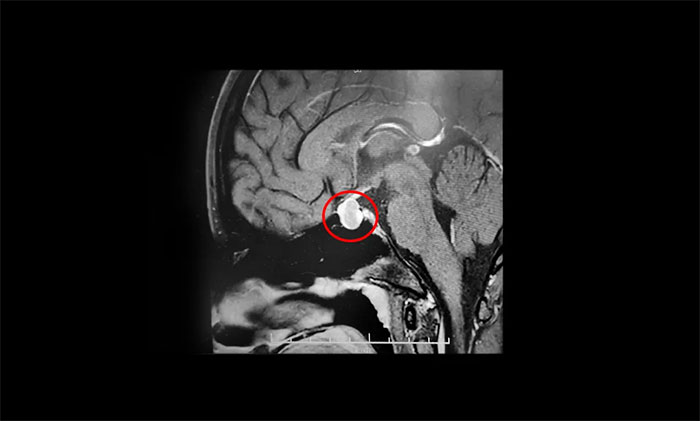

鞍區(qū)MRI顯示:蝶鞍稍擴大,鞍底骨質(zhì)下陷。鞍內(nèi)垂體上緣稍膨隆,腺垂體中央見一枚類橢圓形異常信號,大小約1.6×1.2×0.9cm。

T1WI上呈高信號、T2WI呈低信號,輪廓光整,靜脈團注Gd-DTPA后多個時相動態(tài)增強。冠狀位T1WI見早期病變強化不明顯,與明顯強化垂體對比明顯,病變相對于正常腺體呈低信號,境界變清晰。

垂體柄縮短,未見偏移;視交叉輕度上抬;雙側(cè)海綿竇未見異常改變;所示蝶竇局部黏膜增厚。